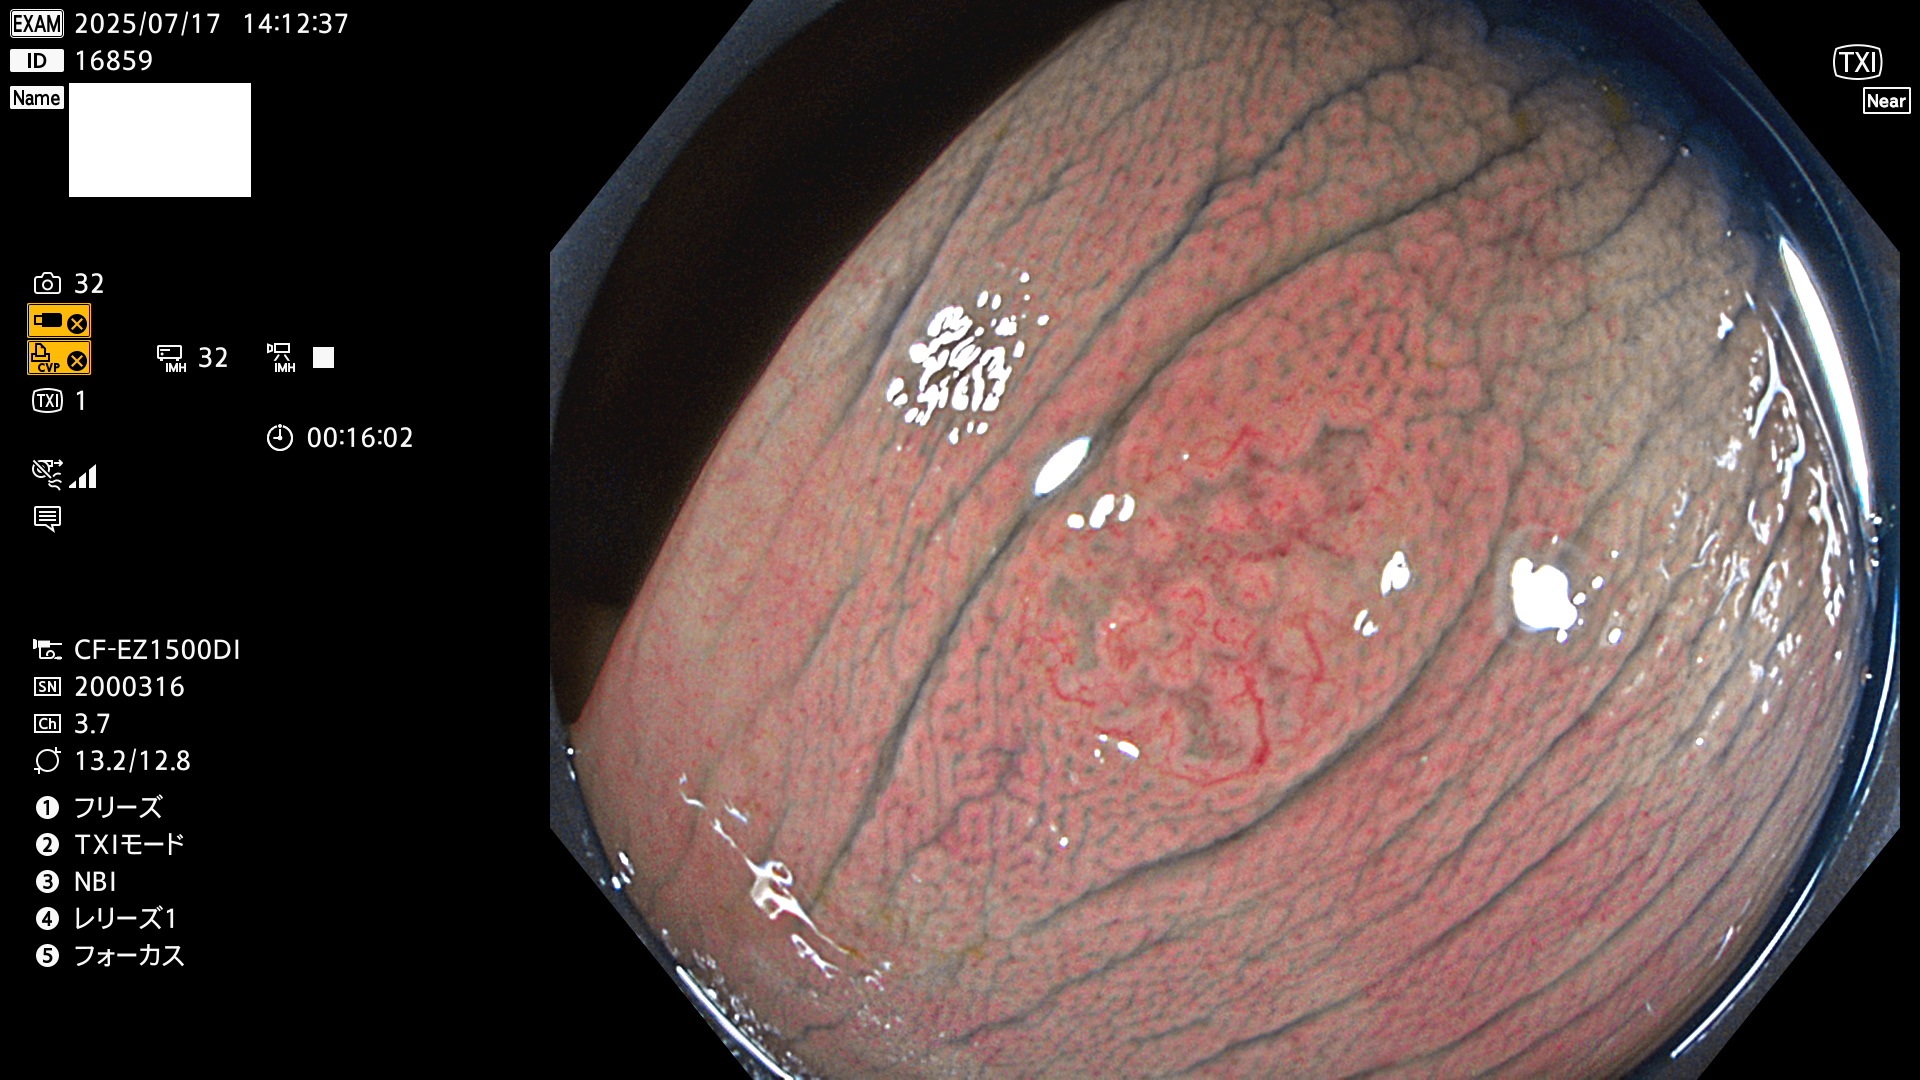

2025年7月17日〜7月20日の4日間(40件)8個 (Uc_ADR=8/40=20%)

びらん(炎症)と紛らわしいUc